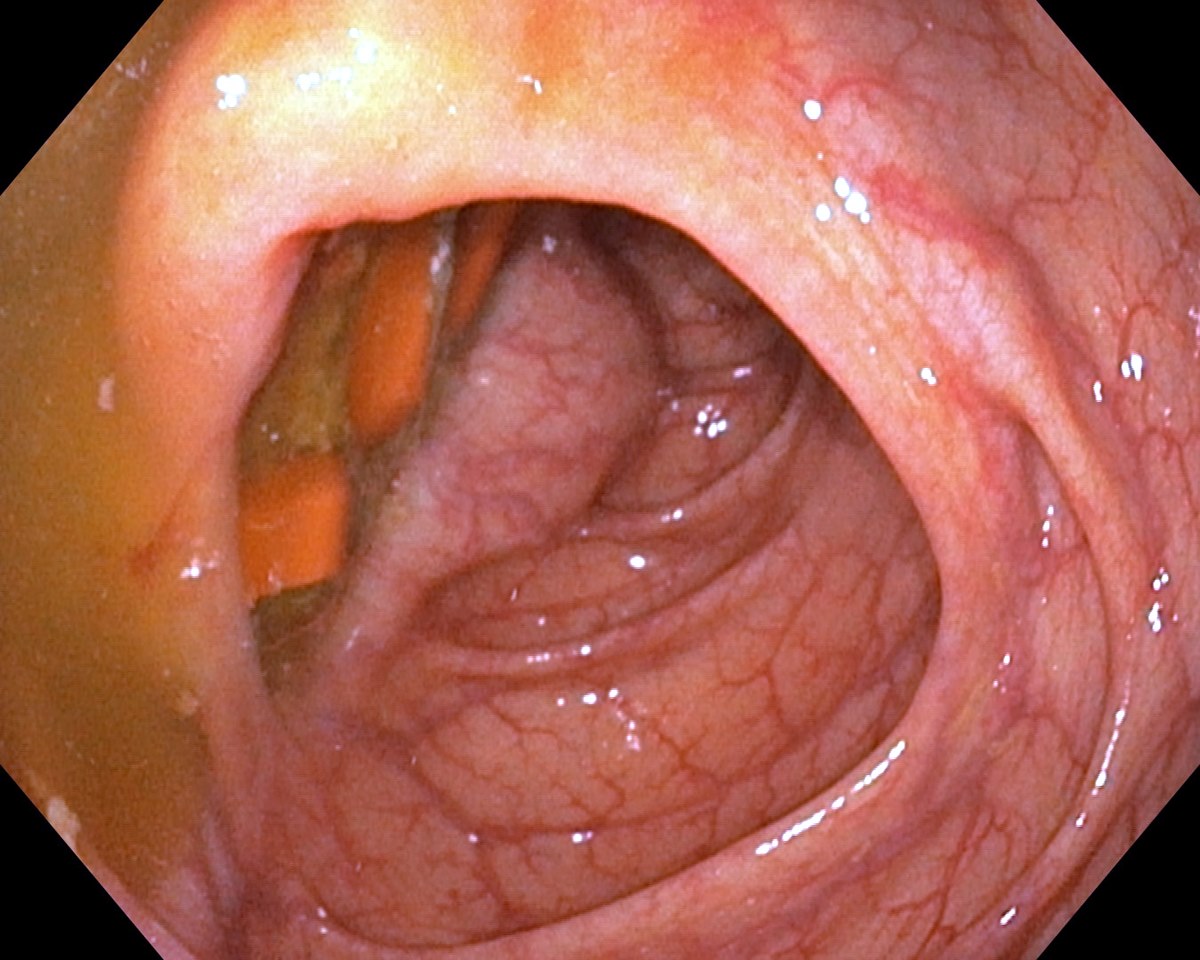

Asacol Tablets in the Caecum, Inactive Ulcerative Colitis

Asacol Tablets in the Caecum, Inactive Ulcerative Colitis. Just click on a picture!